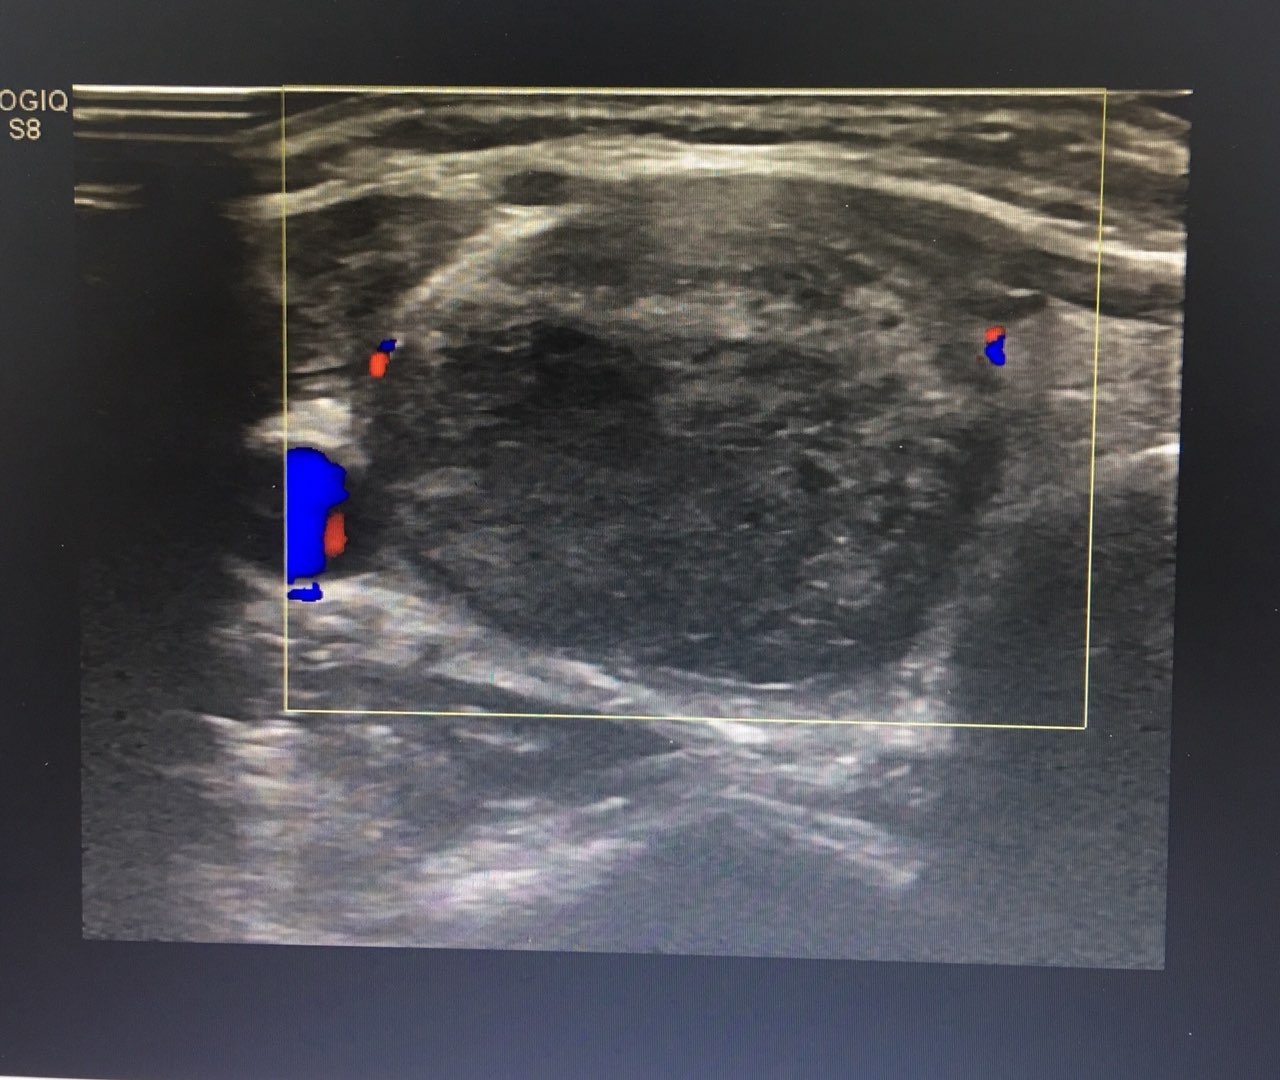

Sau một tháng điều trị, thể tích khối u tuyến giáp của chị Na đã giảm 40%. Hình ảnh siêu âm màu cho thấy không còn mạch máu trong khối u. Chị cho biết: “Khối lồi ở cổ tôi phải nhìn kỹ mới phát hiện ra, không lộ như trước. Tôi không còn đau cổ nữa và cũng ưng ý vì không có sẹo”.

| Hình ảnh siêu âm sắc nét. |

Để đạt hiệu quả chẩn đoán và điều trị tối ưu, Vinmec đã trang bị hệ thống trang thiết bị chẩn đoán hình ảnh hiện đại như máy siêu âm GE Healthcare S9 có đầu dò phẳng, tần số cao, độ phân giải HD cho hình ảnh rõ nét. Kỹ thuật đốt sóng cao tần điều trị u tuyến giáp dưới hướng dẫn siêu âm cho phép bác sĩ kiểm soát được toàn bộ quá trình thủ thuật, tránh tối đa tổn thương mạch máu, thần kinh, khí quản, thực quản... nên an toàn và giảm kích thước khối u tối đa.